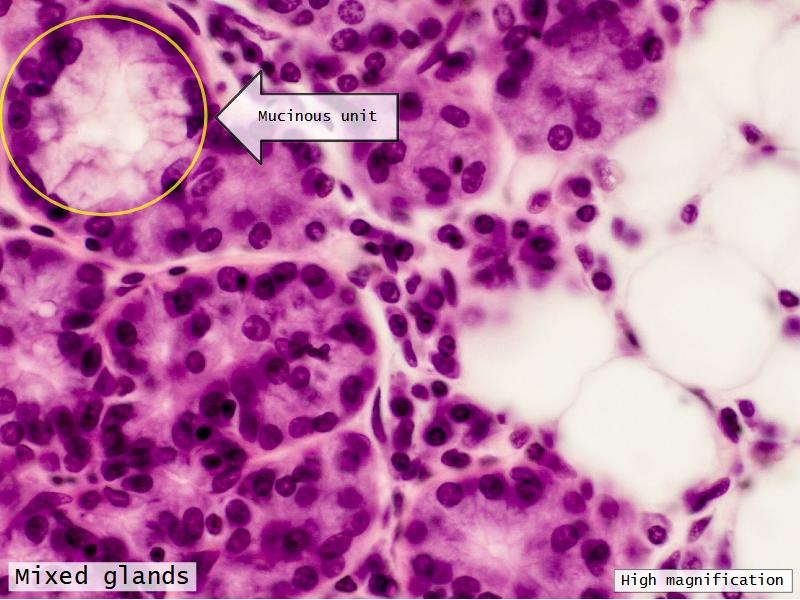

Trachea

Bronchi - Transitions

- Intrapulmonary bronchi

- Irregular cartilage

- Respiratory epithelium

- Glands